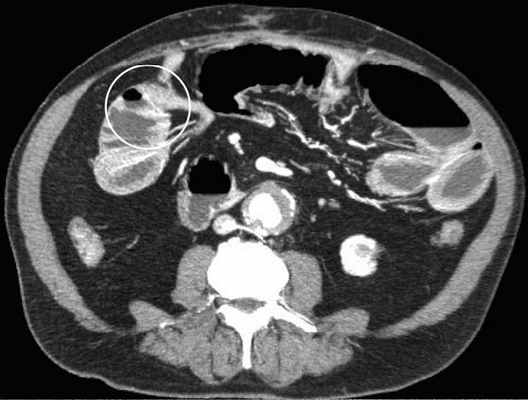

КТ визуализация при простой форме

Хирургическая классификация тонкокишечной непроходимости также является основой классификации, используемой в радиологии. Раличают три формы:

- простая/компенсированная форма

-Расширенные петли тонкой кишки проксимальнее транзиторной зоны (зоны обструкции).

-Под транзиторной зоной надо понимать зонy кишки с очевидной разностью в диаметре просвета между расширенным проксимальным сегментом и местом сужения/обструкции. Визуализация этой зоны зависит от причины и механизма обструкции, а также от проекции расположения петли (аксиально, фронтально и т.д.). К сожалению, обнаружение этой зоны не всегда представляется возможным. При спаечном механизме или воспалении многими хорошо описан признак "птичьего клюва". При обструкции в результате алиментарного болюса транзиторная зона будет выглядеть как гетерогенное образование в просвете кишки без признаков контрастного усиления.

-Спавшиеся петли кишечника дистальнее уровня обструкции.

-Смешанный характер стаза содержимого кишечника в расширенных петлях. Некоторыми авторами описан "фекалоидный" тип стаза, описанный в литературе как "каловое содержимое тонкой кишки", в английской литературе-“small-bowel faeces sign”. Патогенез данного признака включает в себя много факторов:

замедление пассажа содержимого, нарушения механизмов абсорбции и секреции в тонкой кишке, рефлюкс из толстой кишки из-за недостаточности илео-цекального клапана, постановка желудочного зонда. Необходимо помнить, что этот признак неспецифичен при тонкокишечной непроходимости, его также можно определить на УЗИ и обзорной рентгенограмме брюшной полости.

-Нормальные неутолщённые стенки кишечника с гомогенным одинаковым контрастным усилением.

-В тощей кишке рисунок ворсинок слизистой (valvulae conniventes) тонкий, и он одинаково выглядят на всём протяжении.

-Отсутствие патологических изменений толстой кишки, толстая кишка как правило спавшаяся или содержит небольшое количество калового содержимого, распределённого по всему просвету.

-Отсутствие воспалительных изменений в брыжейке и внутрибрюшинном жире.

-Нормальная васкуляризация сосудов брыжейки.

-Отсутствие свободной жидкости в брюшной полости.

Различные КТ сканы при простой форме обструкции, cxематично изображены транзиторные зоны и спайки, которые как "хомут" или "удавка" как-бы душат петлю кишки.